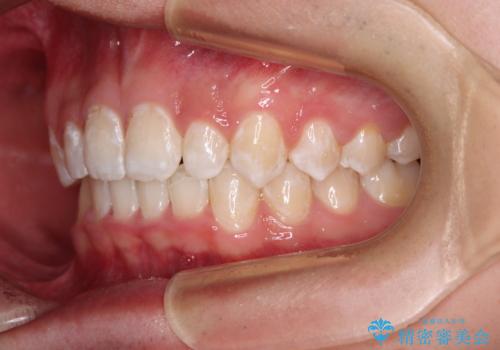

- 強い咬み合わせと前歯のデコボコを気にして来院された患者様です。

下顎前歯が全て隠れてしまうほどの深い咬合で、左右の奥歯は1歯対1歯で咬み合う状態でした。

前方に移動している上顎臼歯を補助装置にて遠心移動させることで1歯対2歯の臼歯咬合を目指し、同時に深い咬合を改善していくこととしました。

このような咬み合わせの場合、治療期間は2年以上がかかることが一般的で、3年程度かかることもありえるケースです。

強く深い咬み合わせにより下顎装置は頻繁に脱離するため、治療期間が長くなりますが、予定通りに終了させることができました。